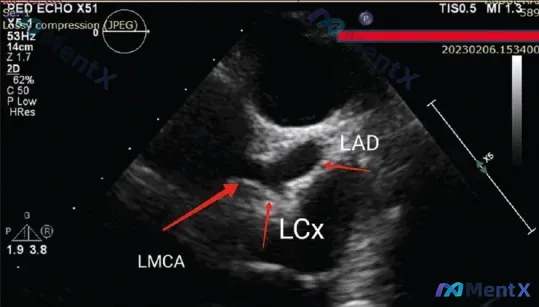

核心线索只有一句话:左冠状动脉系统显著扩张(LMCA、LAD、LCx均受累)。

附带了一张经胸超声心动图(TTE)胸骨旁短轴切面,标注清晰能看到左主干及其分叉;但有意思的是,最初的静态影像分析还写了“管腔未见明显异常扩张”,和前面的核心线索直接矛盾。